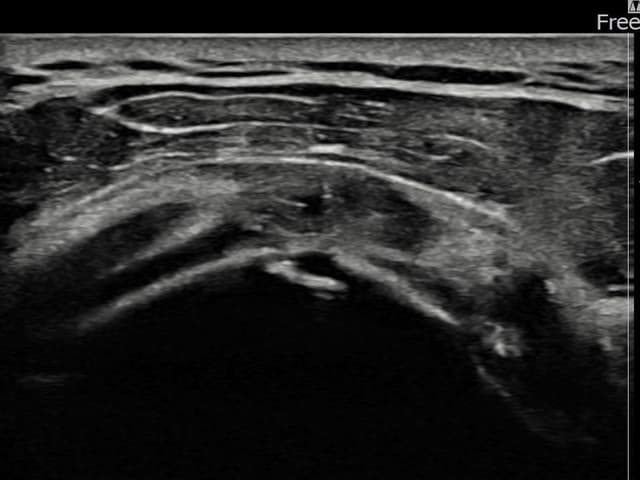

[経過期間: 23.11.09~24.01.18]

[縫縮術] 超音波検査にて左 棘上筋腱 付着部部分断裂(9mm × 4mm (腱厚の約38%欠損))を確認。縫縮術施行後、腱の連続性が回復し、日常生活に復帰されました。